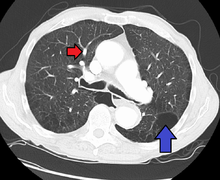

Pulmonary artery hypertension and emphysema as seen on a CT scan with contrast

Signs of pulmonary hypertension on CT scan of the chest are:

• Increased ratio of the diameter of the main pulmonary artery (pulmonary trunk) to the ascending aorta (measured at its bifurcation).

• A ratio of 1.0 is suggested as a cutoff in adults.[59]

• Cutoff ~1.09 in children.[59]

• Increased diameter ratio of segmental arteries to bronchi. This finding in three or four lobes, in the presence of a dilated pulmonary trunk (≥29 mm), and absence of significant structural lung disease confers a specificity of 100% for pulmonary hypertension.[59]

• Mural calcification in central pulmonary arteries is most frequently seen in patients with Eisenmenger's syndrome.[59]